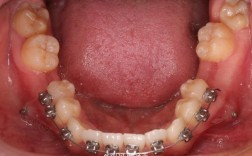

对于拔除前磨牙的病例,关闭间隙时需通过弓丝与结扎丝的配合,将磨牙向近中移动,绞钢丝在此过程中承担“传递者”角色:它将弓丝产生的牵引力传递至磨牙托槽,推动磨牙移动;通过调整结扎的松紧度(如“滑动法”结扎时保持适度张力,避免力量过大导致牙根吸收),确保磨牙沿预设方向移动(如垂直向压低或近中整体移动),在下颌拔牙病例中,若需将下颌磨牙向近中移动关闭间隙,医生会用0.25mm的绞钢丝将磨牙托槽与弓丝紧密结扎,通过弓丝的“滑动”机制实现间隙关闭。